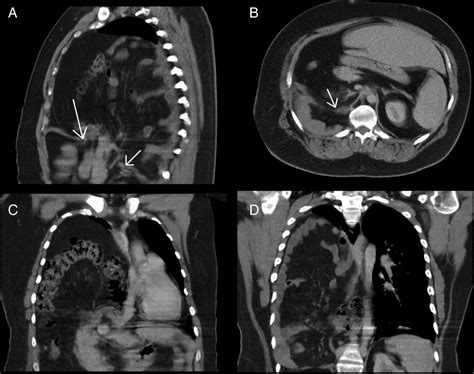

Chest X-ray: Provides a basic view of the chest and can show the presence of a hernia.

CT Scan: Offers detailed images of the chest and abdomen, helping to identify the location and size of the hernia.

MRI: Provides detailed images of soft tissues and can help identify the hernia and its effects on surrounding structures.